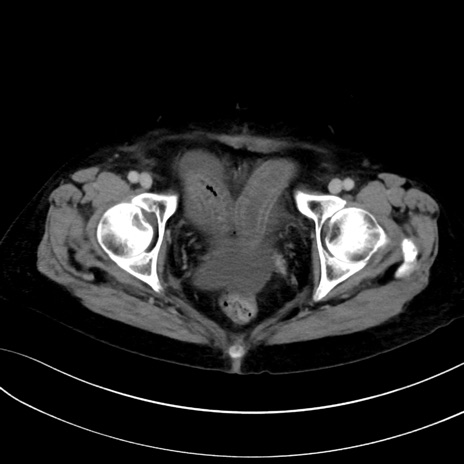

症例13 CT(横断像)1日半後